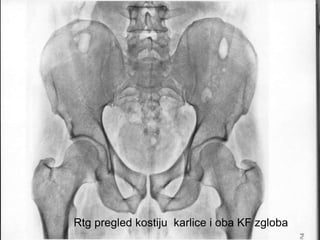

Šematski

prikaz

kostiju

karlice i

oba KF

zgloba

Kosti karlice sa oba kf zgloba

Rtg pregled kostiju karlice i oba KF zgloba